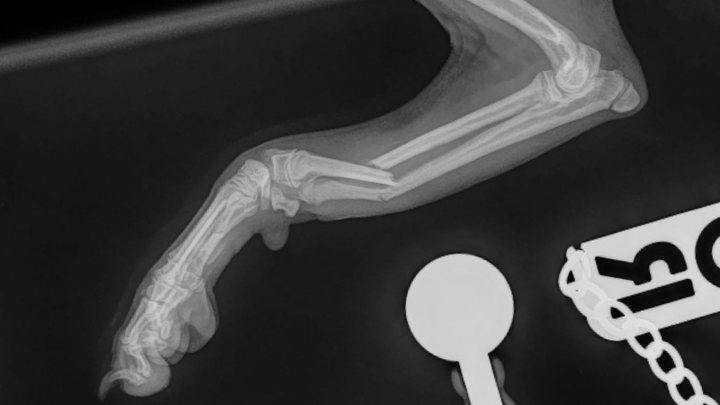

Right now, our hearts are breaking. While playing, Youki broke his leg. It has been temporarily splinted, but the orthopedic vet told us that without surgery his leg may not heal properly. Hearing that was devastating. The operation and costs £5000, and despite our desperate efforts, the insurance company cannot cover it. We are heartbroken because we simply cannot afford this amount, yet we know surgery is his best chance to recover and live the joyful, active life he deserves.

He is only 5 months old. Instead of enjoying walks, socialising with other dogs, and learning through puppy training, he is in pain and missing out on the precious early experiences that shape a happy and confident dog. It’s crushing to watch him confined and hurting, when he should be out exploring the world.